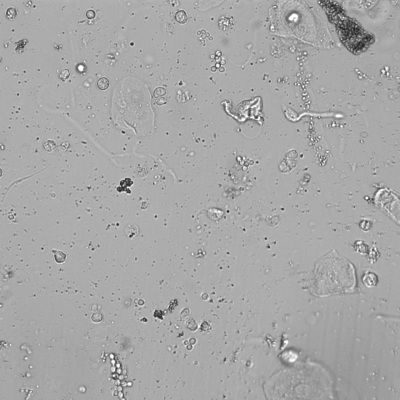

Klarer Harn

Auf diesem und den anderen Bildern dieser Harnprobe lassen sich keine zellulären oder kristallinen Bestandteile finden. Nachdem auch der Teststreifen keine Auffälligkeiten zeigt, wird normalerweise ein solcher Harn selten im Mikroskop kontrolliert.